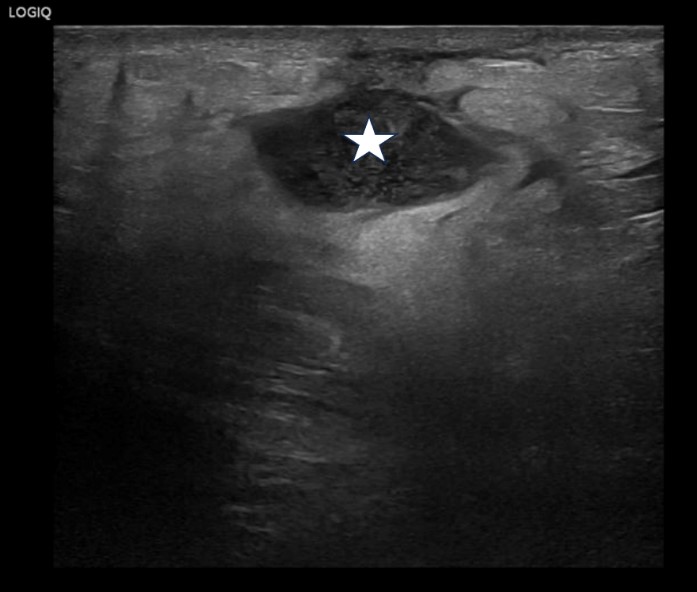

B-mode ultrasound demonstrated gross left sided hydronephrosis with thinning of the renal cortex which is in keeping with previous imaging (fig1). However, deep to the clinically obvious swelling on the left flank there was an irregular heterogeneous fluid collection which extended from the superficial soft tissues/skin to the lower pole region of the left kidney with which it appeared intimately associated (fig2, fig3 and Fig 4). These findings were concerning for a large renal abscess which may have progressed to a perirenal abscess and developed a sinus tract extending to the skin surface. In light of the elevated CRP, urgent cross-sectional imaging and urgent clinical review by the urology team was conducted. The right kidney and urinary bladder were unremarkable on ultrasound.

| Figure 3: Sinus tract extending from the left kidney through the posterior abdominal fascial planes (Star: Intraperitoneal aspect of the sinus tract, Triangle: Subcutaneous aspect of the sinus tract) |